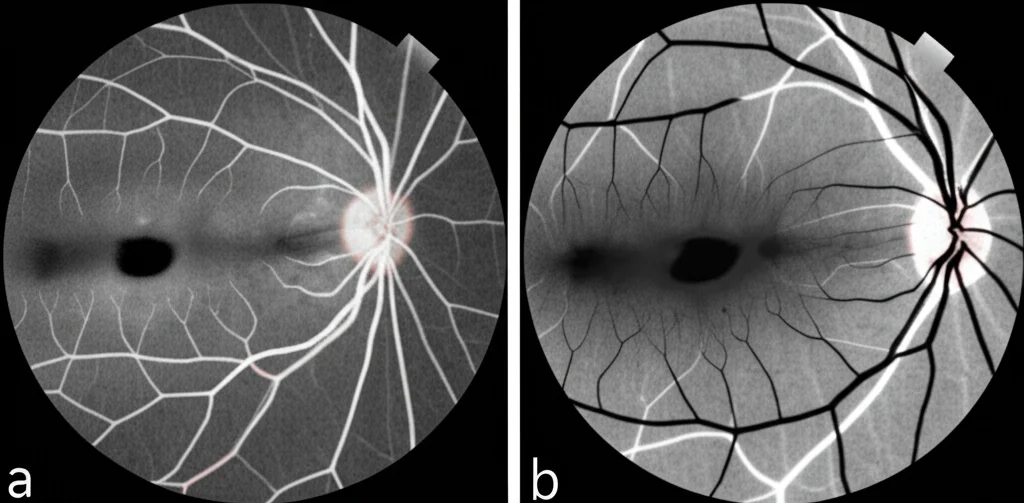

Per classificarle, gli esperti usano un sistema chiamato META-PM (International Photographic Classification and Grading System for Myopic Maculopathy), che suddivide la MMD in categorie da C0 a C4:

- C0: Nessuna lesione degenerativa retinica miopica.

- C1: Fondo oculare a mosaico (Tessellated fundus).

- C2: Atrofia corioretinica diffusa.

- C3: Atrofia corioretinica a chiazze (Patchy atrophy).

- C4: Atrofia maculare completa.

Più si sale di categoria, più la situazione è seria e maggiore è il rischio di perdita visiva irreversibile. Ecco perché capire i fattori di rischio e i meccanismi di progressione è cruciale.